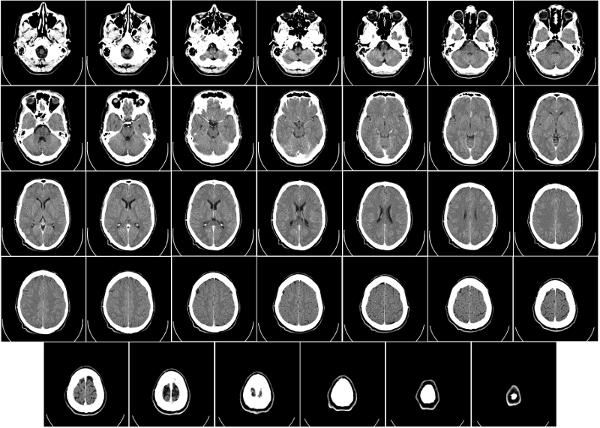

Resultado de la tomograf a computacional

Tomograf a computacional (TC)

Soluci n de Hundsfield

Soluci n del problema matem tico